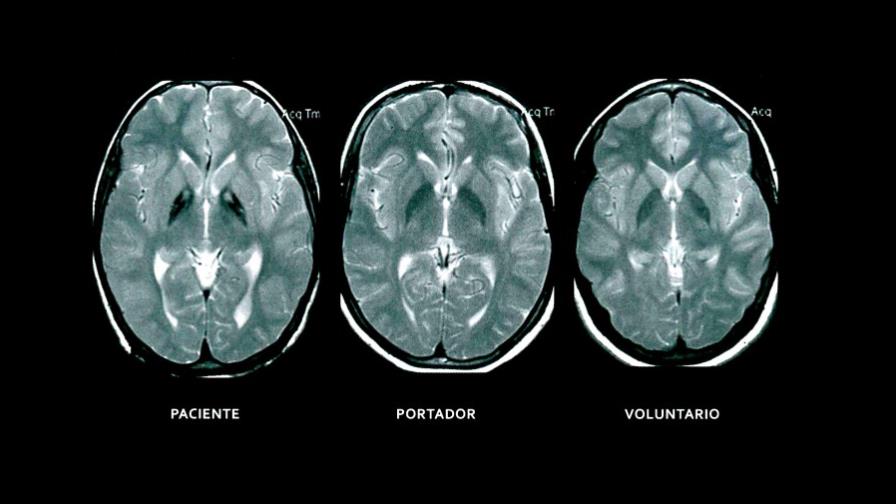

This pathology forms part of some neurodegenerative cerebral conditions, in which the deposit of iron in the brain is severe. It is transmitted by the genes from parents who are carriers and begins to present in early childhood - 3 ½ to 6 years-and sometimes as late as 10 to 14 years. When the patients undergo a magnetic resonance a sign called "Eye of the Tiger"is discovered, a dark area that the doctors say appears to be the face of that animal.